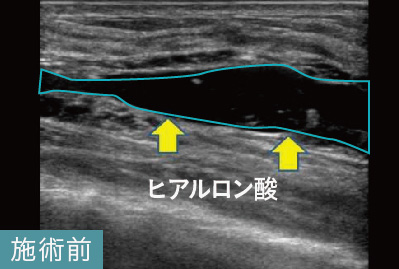

吸収されなかったヒアルロン酸がエコーで黒い塊として映し出されており、しこりと確認できます。

このケースは、他院でヒアルロン酸溶解注射による治療を受けても残ってしまったしこりの治療でした。しこりの取り残しは、治療前にしこりの正確な位置を把握していなかった可能性が考えられます。当院では、実際にしこりを確認しながらヒアルロン酸内に的確に注射を行います。このケースでも完全になくなっていることが確認できます。